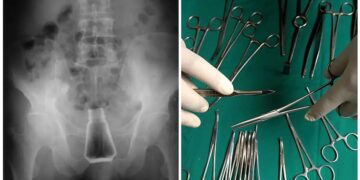

Σοκαρισμένοι μπροστά στο θέαμα που αντίκρισαν ήταν οι γιατροί και οι νοσηλευτές του νοσοκομείου Σύρου, όταν έφτασε ένας ασθενής από τη Μήλο, ο οποίος είχε στον πρωκτό του ένα μπουκάλι αλάτι.

Ο ασθενής μεταφέρθηκε εσπευσμένα στο νοσοκομείο της Σύρου, καθώς κινδύνευε η ζωή του.

Οι πληροφορίες του logotypos.gr αναφέρουν ότι ο εν λόγω άνδρας είχε για δύο ολόκληρες ημέρες στον πρωκτό του το μπουκάλι με το αλάτι, καθώς ντρεπόταν να πάει σε γιατρό. Όπως αντιλαμβάνεστε, υπήρχαν φόβοι να πάθει σηψαιμία.

Αμέσως, ο ασθενής από τη Μήλο μπήκε στο χειρουργείο και του αφαιρέθηκε το αντικείμενο που υπήρχε στον πρωκτό του, προτού υπάρξουν πιο δυσάρεστες συνέπειες για την υγεία του.